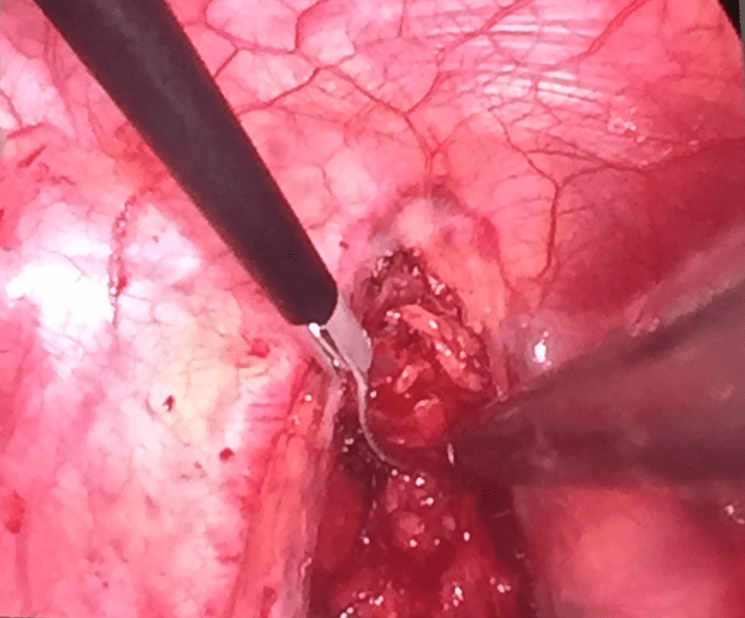

Grande Morales, Carlos E.; Galizia Brito, Victoria; Expósito Pineda, Maria del Carmen; Bibiloni Cladera, Aina; Falco Martinez, Teresa; Peral Disdier Vicente [Descargar PDF] Resumen. El cardiodesfibrilador implantable (CDI) es efectivo en el tratamiento de arritmias...